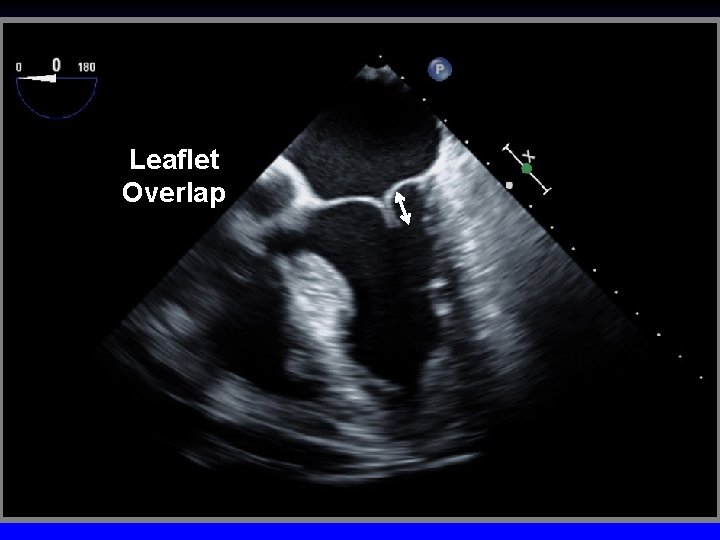

Leaflet Overlap

Tenting area Coaptation depth Leaflet overlap